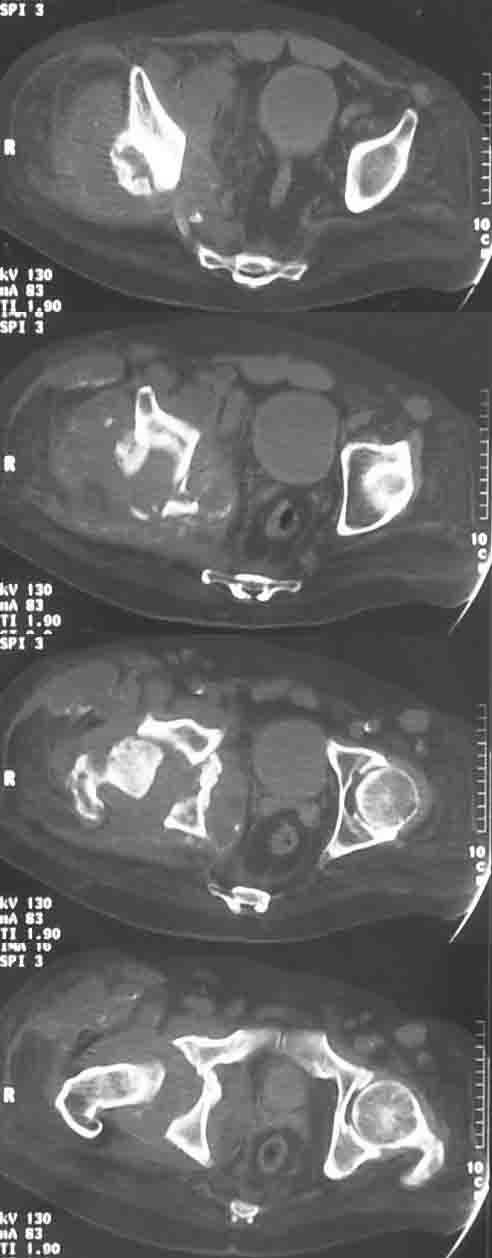

Дрогие коллеги, Обратился пациент, М-44, с опухолью правой тазовой кости, однако не все пока укладывается в обычное течение:

относительно медленный рост, нет интоксикации, нет снижения веса, нет метастазов, очень плотная ткань, при гистологическом исследовании после широкой открытой биопсии видны лишь элементы воспаления, фиброз, хрящевые включения. Рана зажила первично. В анамнезе тромбоцитемия, оперирована грыжа Шморля, практически нижний парапарез.

Может есть какое-то специфичекое поражение костей, когда такая рентгенологические проявления? С уважением, И.И.